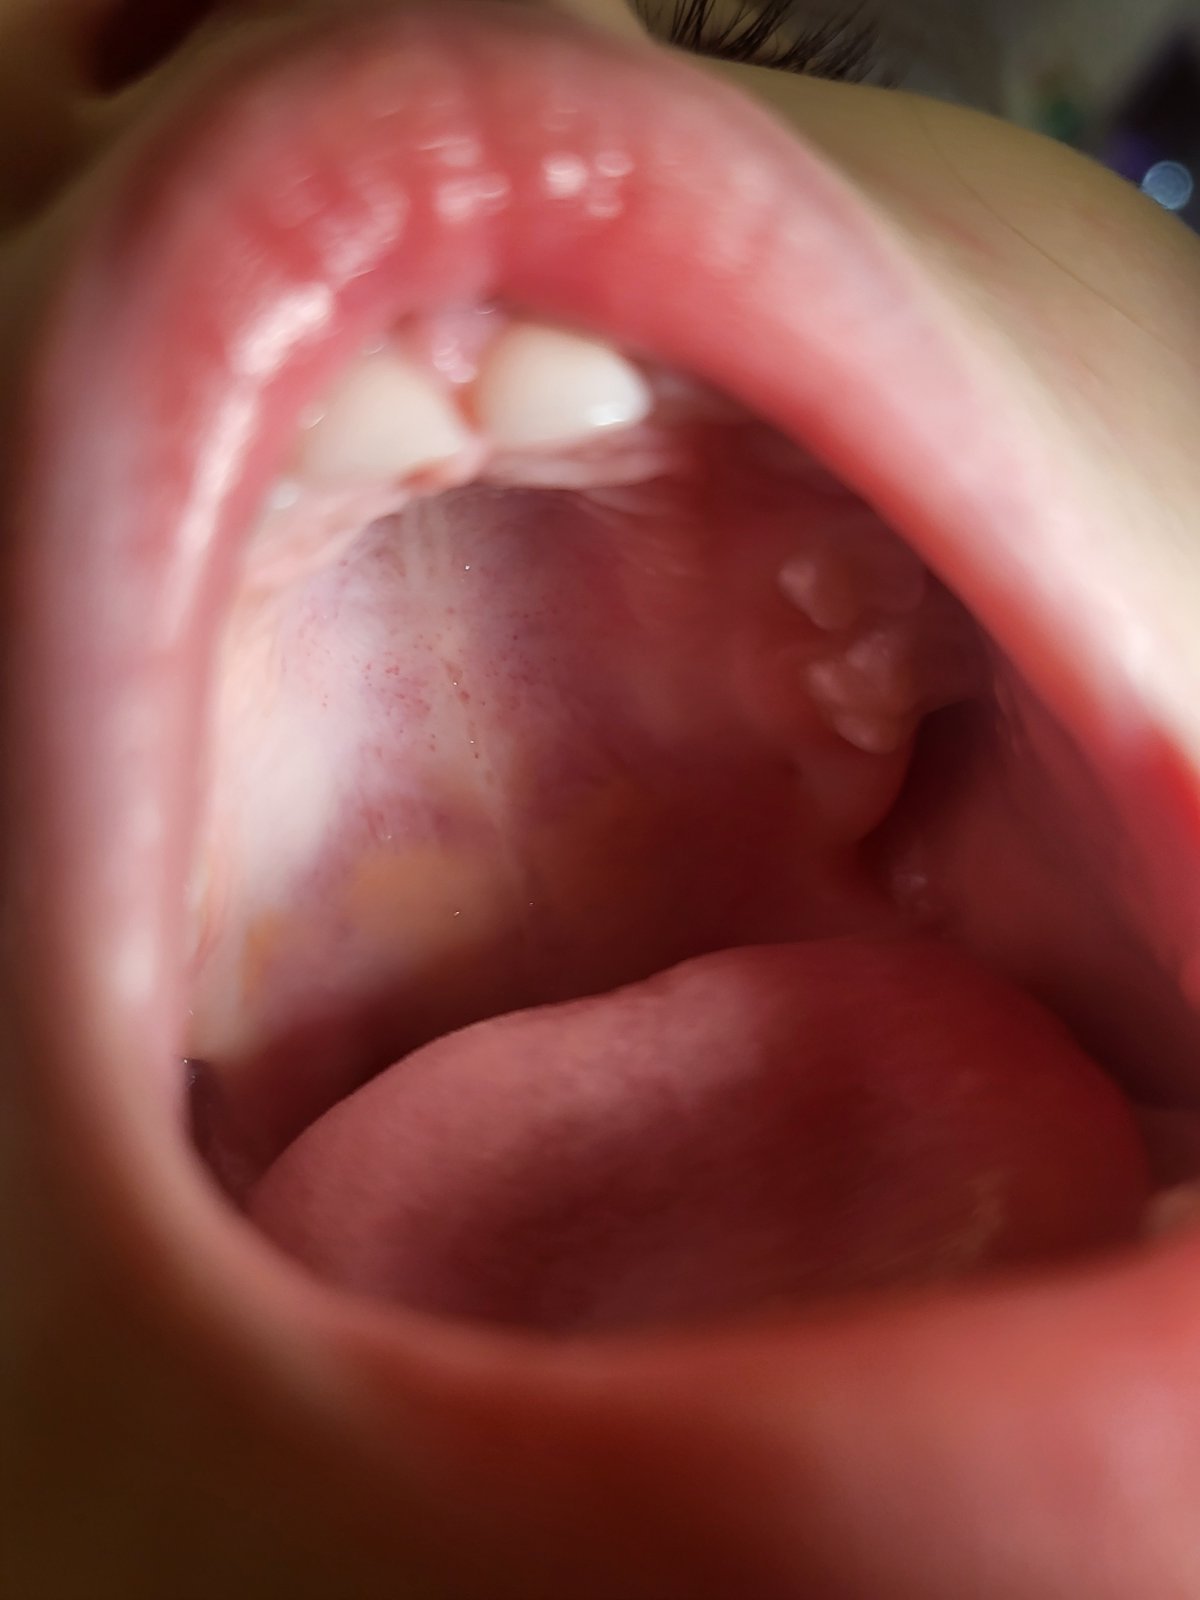

Dobry den, 4 rocna dcera sa od stvrtka stazovala na bolest podnebia. Ma tam taketo bodky. Dala som tantum verde +b vitamin. Bolest presla, bodky este su. Neviete, co to moze byt?

Teplotu nema, pije a je normalne. Hrdlo ciste, ziadne dalsie priznaky....

Lepsie foto